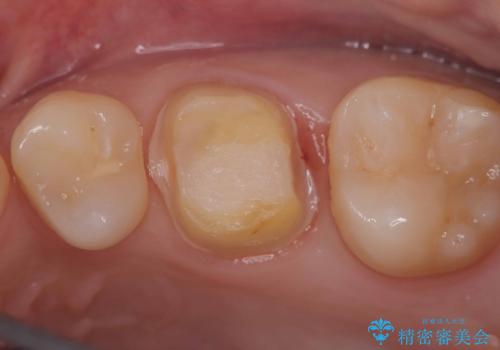

- 虫歯が神経まで達していたのですが、術前の検査と顕微鏡下で見た神経の状態からVPTの適応と判断し神経を残す治療をしました。

汚染されている神経は除去し残りの神経を残すためVPTを行いバイオセラミックのバイオシーシーラーで充填しオールセラミッククラウンで治療を行いました。治療後2年経過しましたが、神経は温存され経過は良好です。